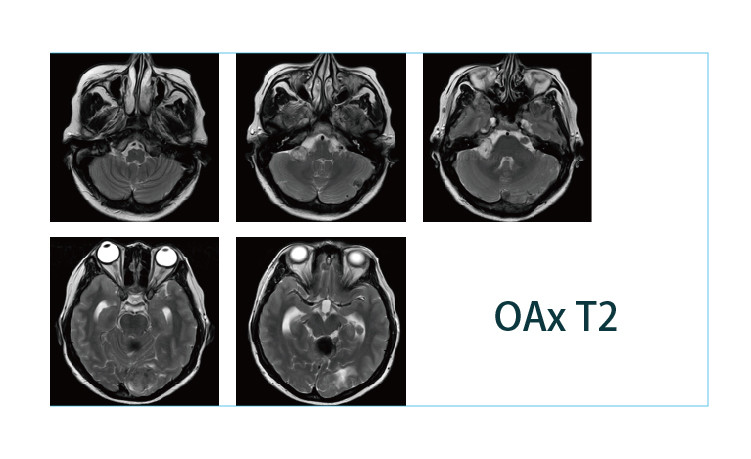

【朗润影像档案】磁共振影像病例分享(编号20190412)